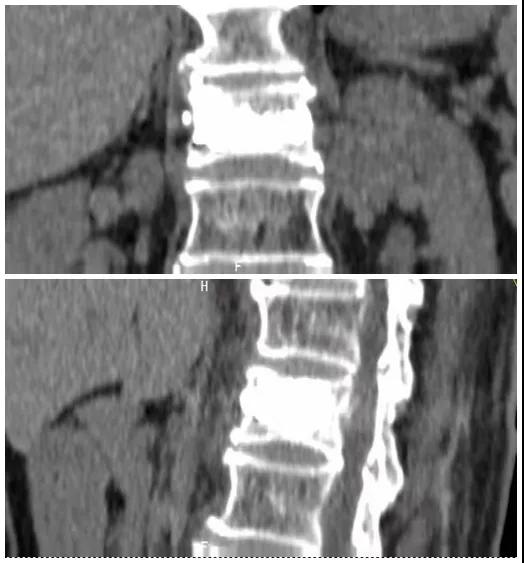

術(shù)前磁共振檢查提示腰1椎體新鮮壓縮性骨折

術(shù)后復(fù)查CT可見骨水泥彌散充分

經(jīng)術(shù)前分析詳細(xì)評估,由骨科副主任張宏宇及科室團(tuán)隊(duì)順利為患者進(jìn)行了經(jīng)皮穿刺椎體成形術(shù),術(shù)后患者疼痛明顯減輕。同時,科室團(tuán)隊(duì)還為她制定了科學(xué)的抗骨質(zhì)疏松治療,目前患者已康復(fù)出院。